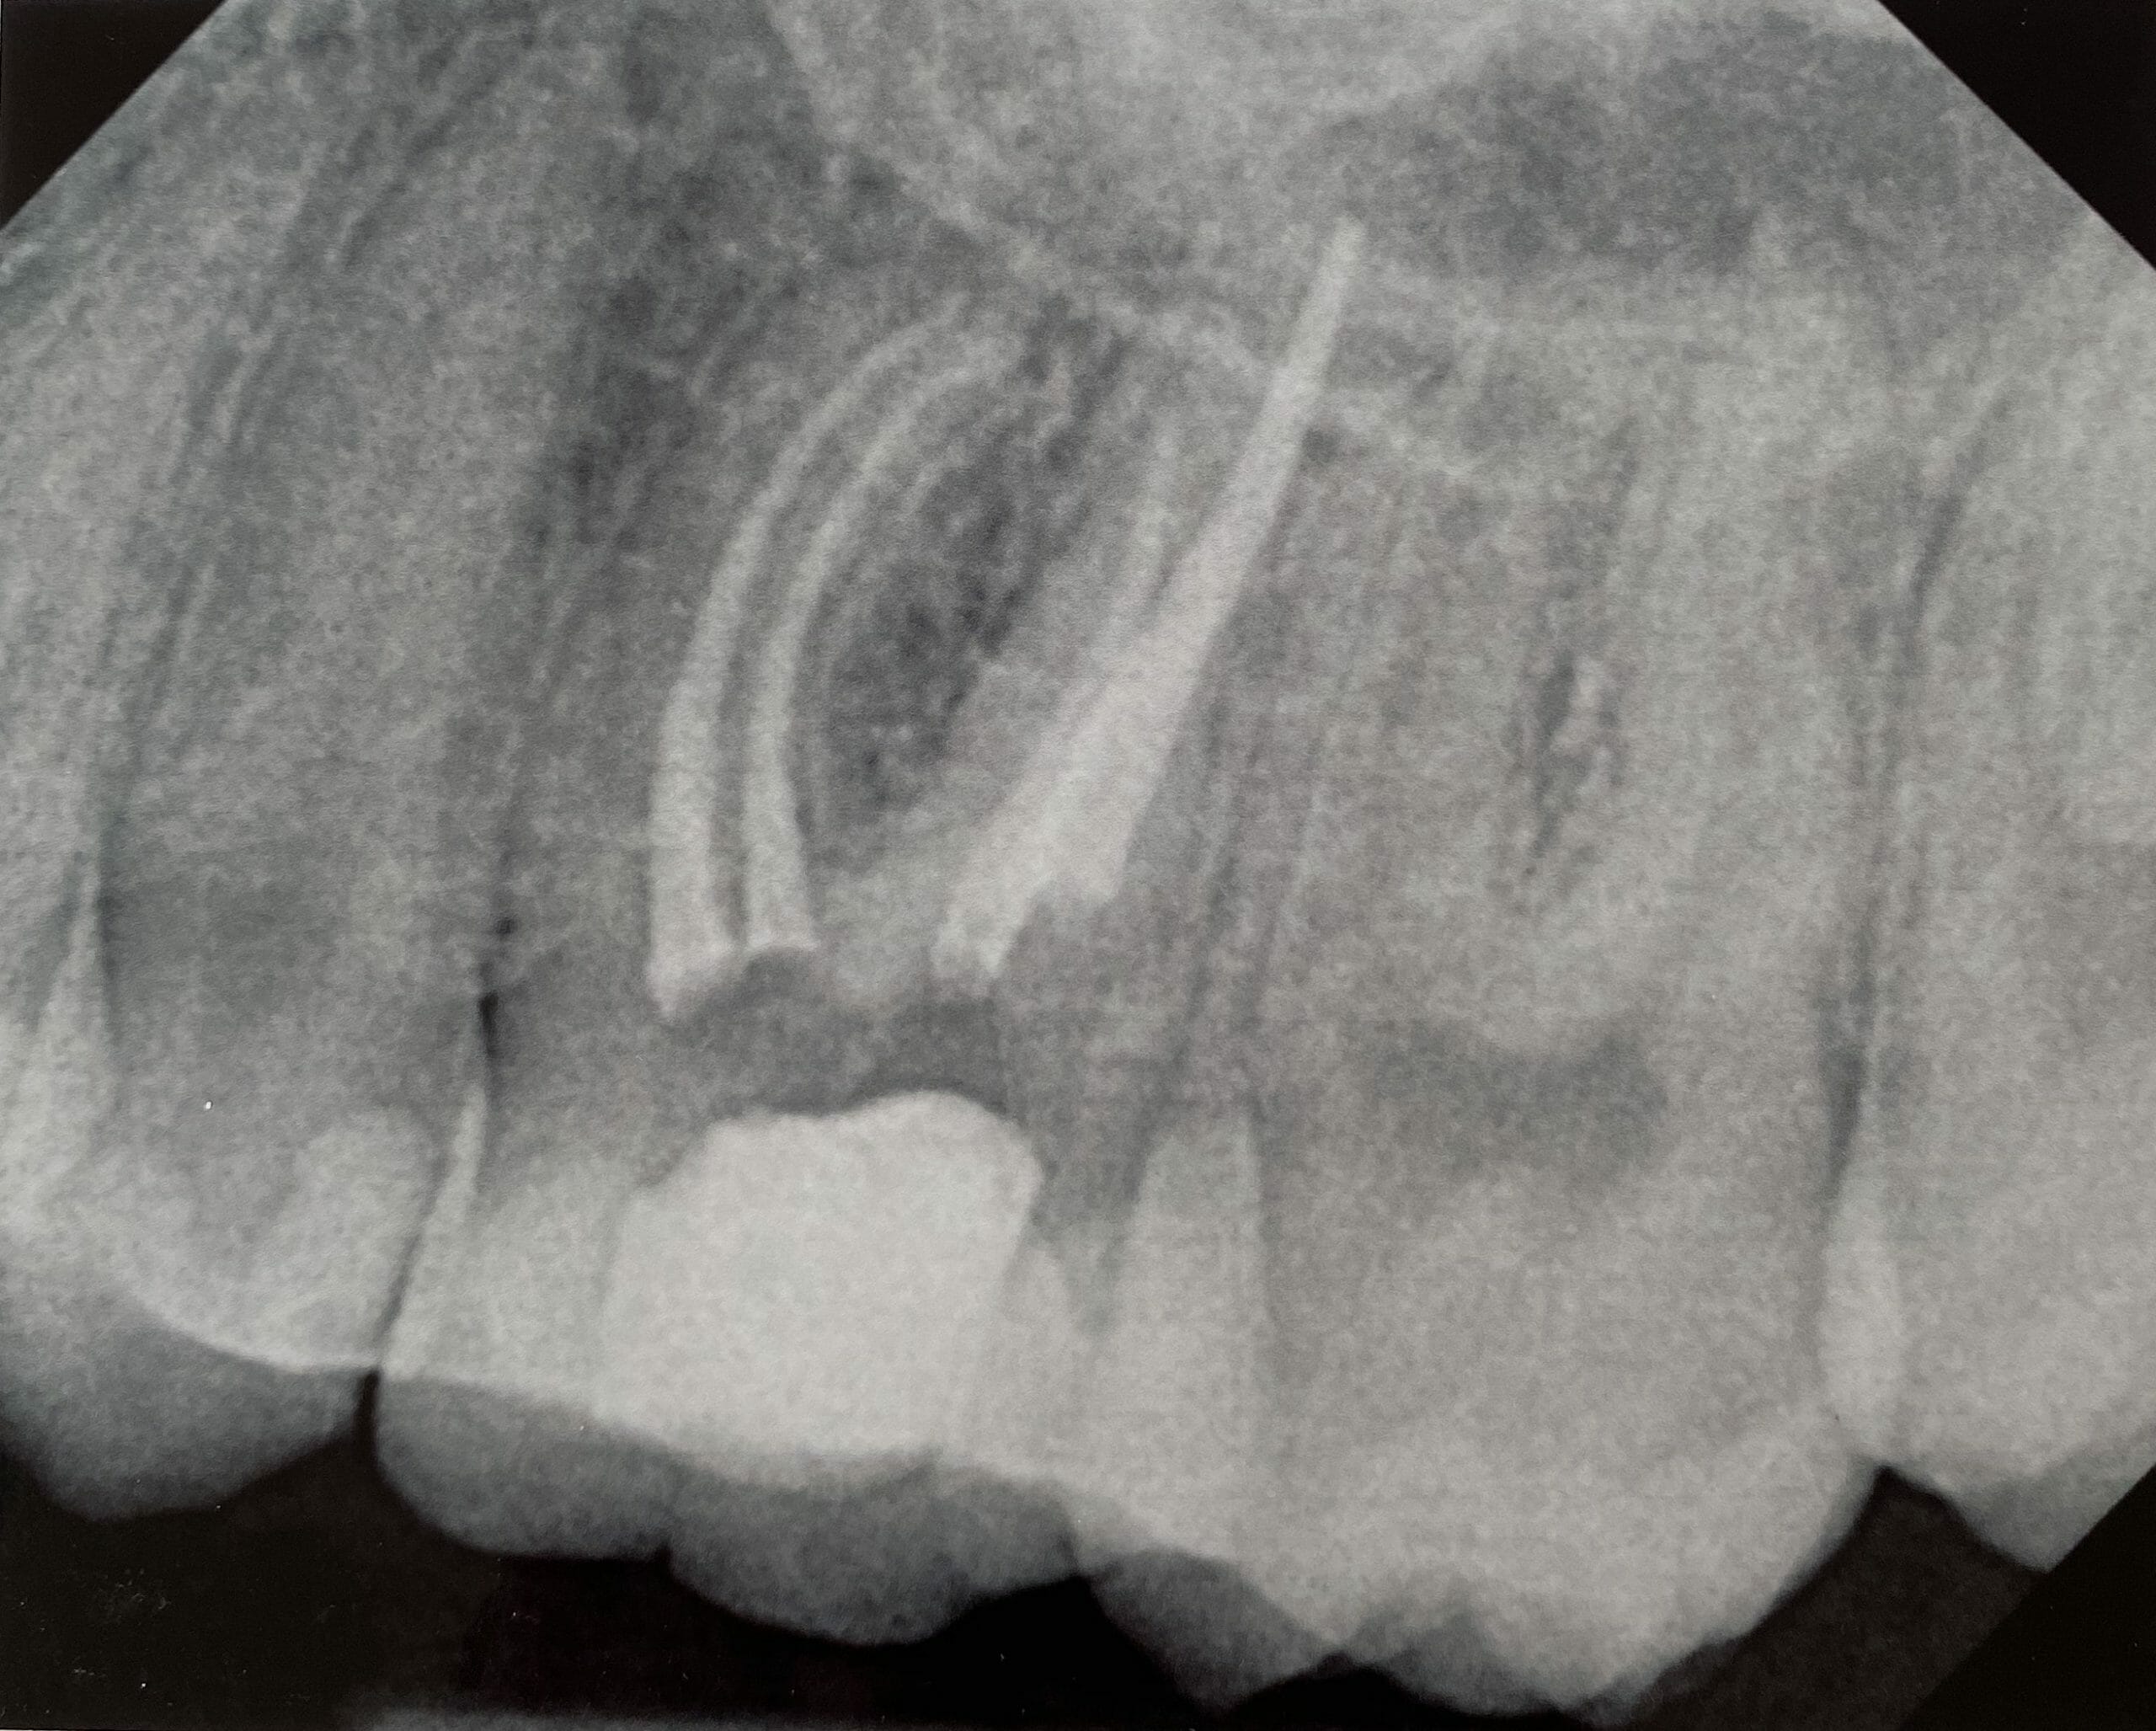

Root Canal Treatment

Click on an x-ray image below to see a larger version:

Maxillary Premolar With Three Canals

Apical Root Resorption

Retreatment Molar Pre-op and Post-op